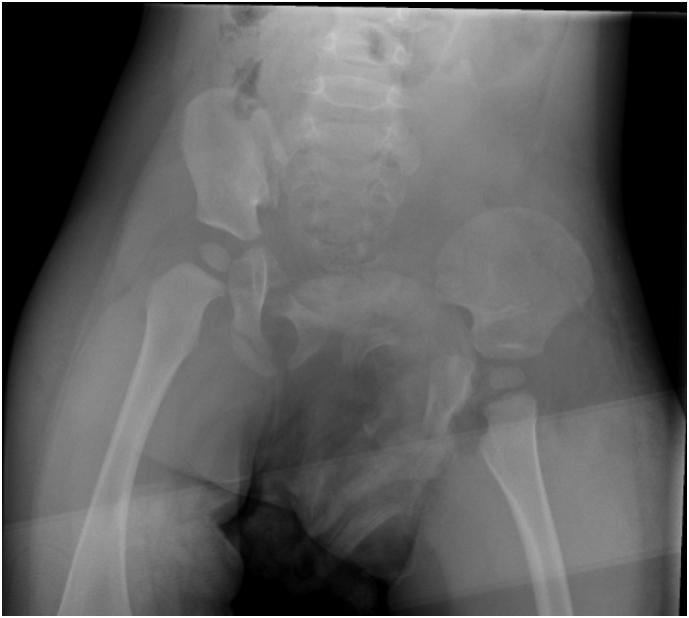

We report on a 14 months old toddler who sustained a traumatic hemipelvectomy by being crushed between a car and a stone wall. After stabilization in the resuscitation room he was treated operatively by laparotomy, osteosynthesis of the pelvic ring, reconstruction of the both external iliac vessels and the urethra and reposition of the testicles. After 66 days he was discharged into rehabilitation. Implants were removed after eight months. 20 months after the injury, the leg was plegic, initial radiological signs of femoral head necrosis showed up but the infant was able to walk with an orthesis and a walker. Up to our knowledge, this is the youngest patient described in the literature with a survived traumatic hemipelvectomy and salvaged limb.